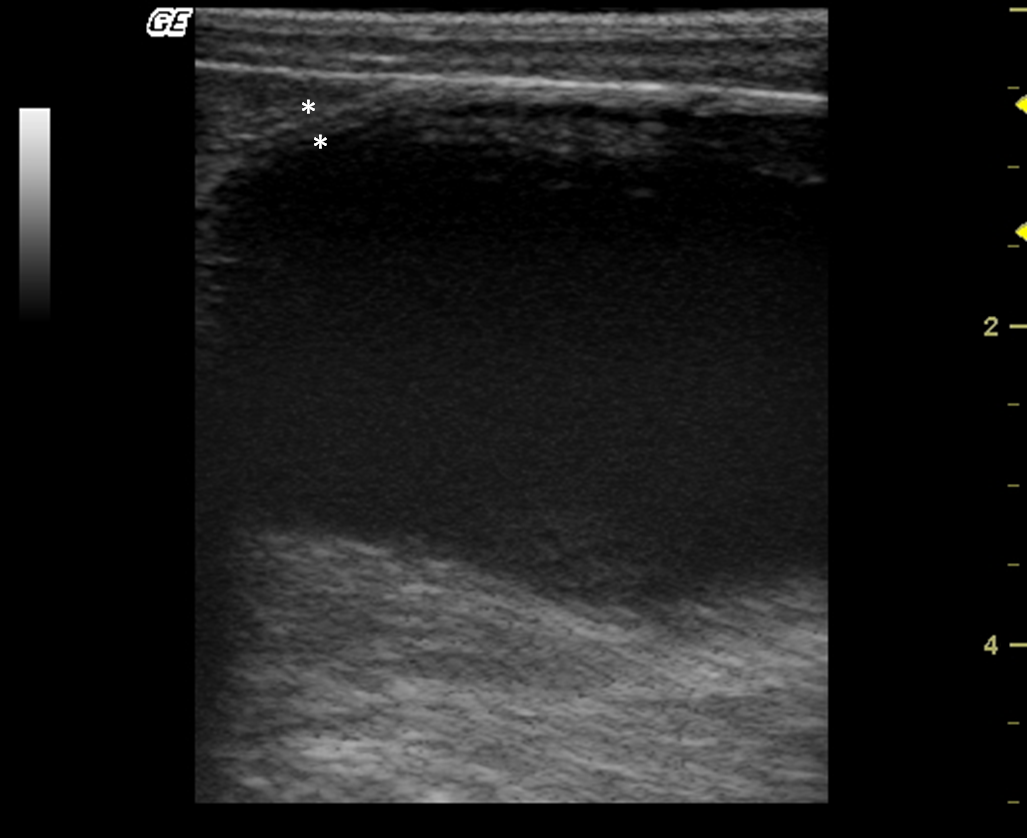

The kidneys were observed in the retroperitoneal space. The left kidney was evaluated caudal to the gastric fundus and the right was identified in the renal fossa of the right liver in all individuals. Kidneys lengths (average of 3.81 cm), are described in Table 1. The renal outlines were well defined and regular, delineated by a thin hyperechogenic line, the renal capsule (Fig. 2a,b). It was possible to identify and delineate the cortical, medullary and renal pelvis regions in all individuals. The cortex showed homogeneous echotexture and it was isoechoic to hyperechoic to the liver parenchyma and isoechoic when compared with the splenic parenchyma. The medullary region was well defined and appeared hypoechogenic in relation to the cortex. The pelvis was hyperechoic in relation to other parts of the kidney, possibly due to the fat present in this region. Discrete pyelectasis (0,2–3 mm) was observed in at least one kidney in five monkeys. This finding is assumed to be due to the fluid therapy or a normal variant. The relationship among cortical and medullary regions was measured, averaging proportion of 1:1. Post-mortem study of the kidneys allowed a better understanding of the anatomy (Fig. 2c,d). Medullary rim sign was not observed in any individual.

|

Figure 2. (a,b) Sonogram of the kidney in frontal (a) and sagittal (b) image planes. (c,d) Post-mortem comparative study of the kidney on a frontal view (c) and sagittal view (d). 1 – Cortical, 2 – Medullar, 3 – Renal pelvis. |